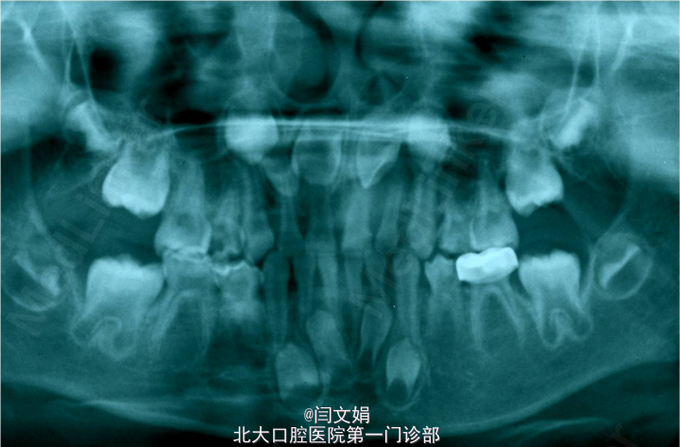

全口卫生状况较差,牙面大量软垢。 75MOBP大面积龋坏,色棕黄,质软,叩痛(-),不松动,牙龈未见红肿瘘管。 X线片示:根尖未见低密度影, 35牙胚未见。 全口曲面断层片示:15,25,35,45,14,24,34,44,1,2,22,32,42恒牙胚未见,11与13间见一畸形牙胚影像。第一二恒磨牙牙胚存,第三恒磨牙未见。21牙胚扭转。

诊断:75MOBP深龋;15,25,35,45,14,24,34,44,1,2,22,32,42先天缺失 处理:75MOBP充填后预成冠修复,治疗其余龋坏牙, 待成年后修复缺失牙

多颗牙齿先天性缺失,需要多学科综合治疗,目前常用正畸方法是关闭间隙、集中间隙或保持间隙以种植体或义齿修复,对于牙槽骨发育不足的多数缺牙和无牙的患者可采用外科手术植骨,术后种植体或义齿修复。 对于该患者多颗牙齿缺失难以采用正畸的方法关闭间隙,需通过以后的修复或种植治疗,在其乳牙列阶段,我们一方面通过治疗防止乳牙早失,另一方面也应密切观察是否有乳牙下沉,一旦发现及时治疗防止其对牙弓发育的影响。预成冠修复适用于乳牙大面积龋坏,对于活髓牙也同样适用。